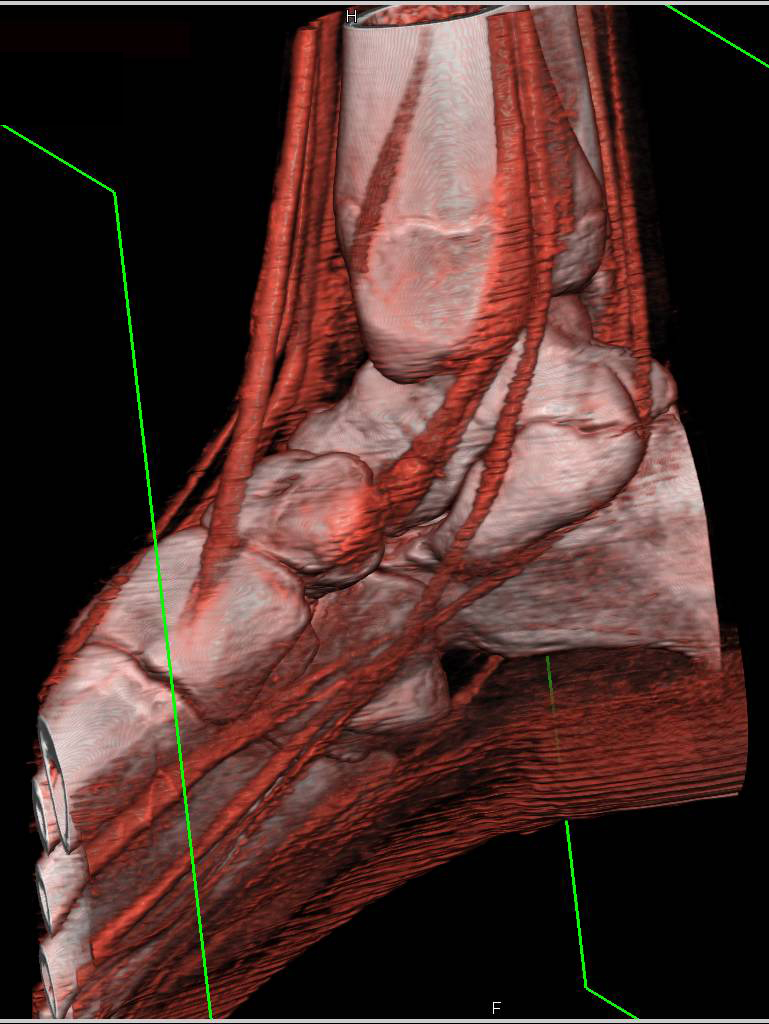

Структура и анатомия синдесмоза: научные иллюстрации